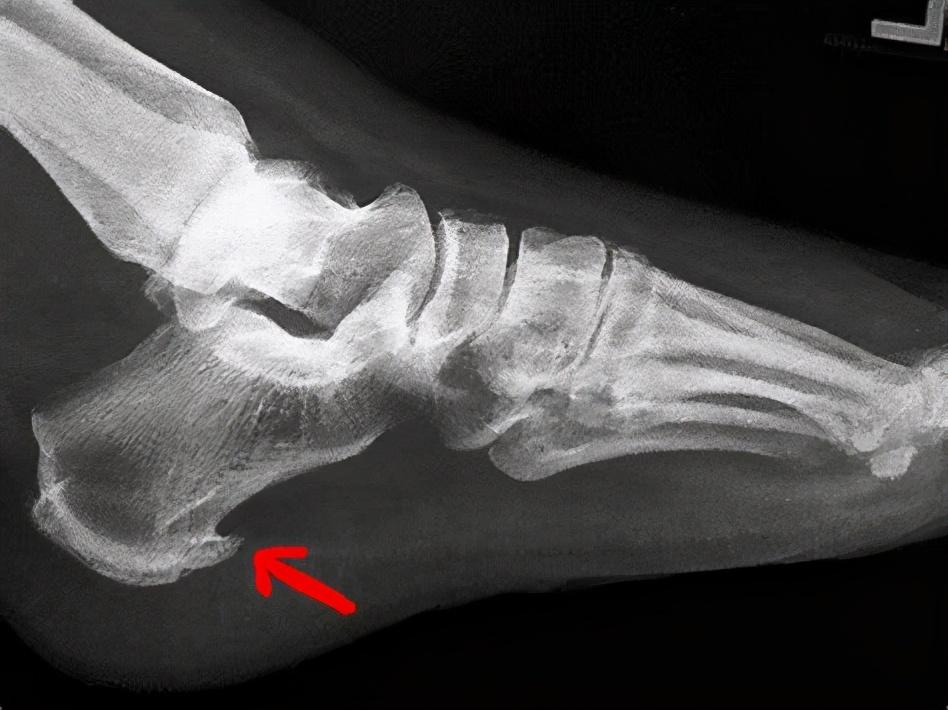

二、骨质增生 。很多人做放射线检查之后都会看到骨头上长着一些尖尖的刺 , 大家都称之为这是骨刺 , 也就是骨质增生 。

很多人觉得骨刺一定要去掉 , 怕扎到自己 , 其实这种想法是不对的 。

从医学上讲 , 骨刺更多的是一种机体的自我保护 , 在有局部摩擦或者受力不均匀的地方就会出现这种骨质增生 。

对于大多数人来说 , 骨质增生不需要治疗 , 因为既没有症状也不会影响到个人的生活 。

但是只有很小部分人会出现严重的疼痛或者神经症状 , 这个时候就需要干预了 。

所以如果发现骨刺 , 也不要自己吓唬自己 , 这没什么可怕的 , 都是正常的 。